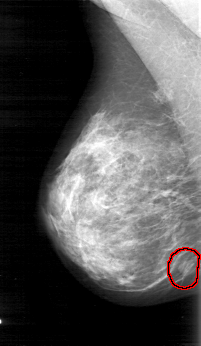

D_4031_1.RIGHT_CC

RIGHT_CC LINES 5206 PIXELS_PER_LINE 3001 BITS_PER_PIXEL 12 RESOLUTION 43.5 OVERLAY

FILE: D_4031_1.RIGHT_CC.OVERLAY

TOTAL_ABNORMALITIES 1

ABNORMALITY 1

LESION_TYPE MASS SHAPE OVAL MARGINS OBSCURED

ASSESSMENT 0

SUBTLETY 5

PATHOLOGY BENIGN

TOTAL_OUTLINES 1

BOUNDARY